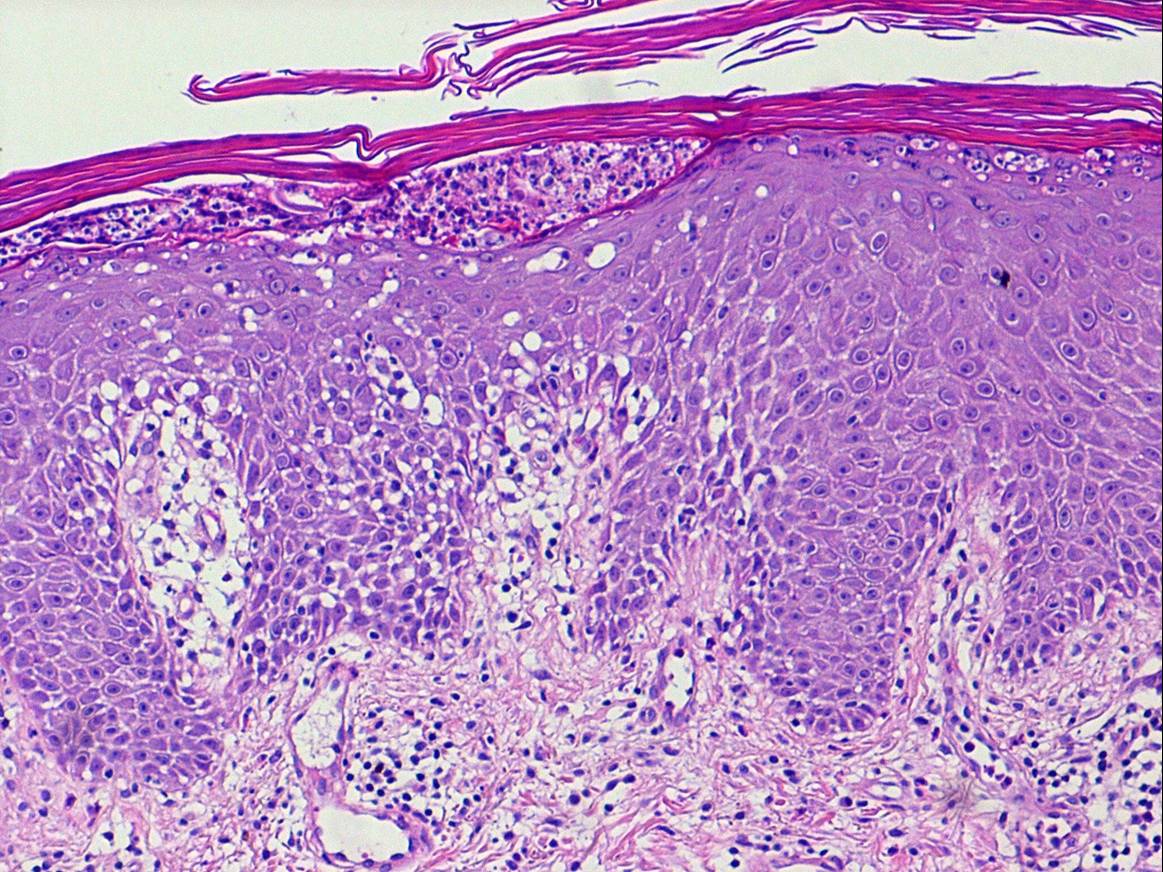

Histopathology.

A careful search for histologic features of any of the above listed etiologies must be undertaken; however, the nature of the underlying dermatosis is not always discernible in the erythrodermic phase, and the changes are often those of nonspecific subacute or chronic spongiotic dermatitis. Erythrodermic lesions associated with underlying psoriasis  resemble early lesions of psoriasis with only mild epidermal hyperplasia, mild spongiosis, mounds of parakeratosis with a few neutrophils, and red cell extravasation in the papillary dermis. Blood vessels in the upper dermis are usually dilated. In cases of erythroderma related to mycosis fungoides, atypical cells with cerebriform nuclei are present in the infiltrate. Eosinophils may be present. Drug-related cases might simulate mycosis fungoides with exocytosis, lymphocytic atypia, and the presence of eosinophils. The presence of rare apoptotic keratinocytes may be a clue to the drug etiology.